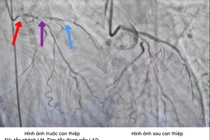

Đau ngực dữ dội, 2 lần ngừng tim liên tiếp do tắc mạch máu chính

Bệnh nhân ngừng tim hai lần trong vòng vài ngày, được cứu sống nhờ xử lý cấp cứu nhanh và hệ thống can thiệp mạch máu hiện đại tại bệnh viện.